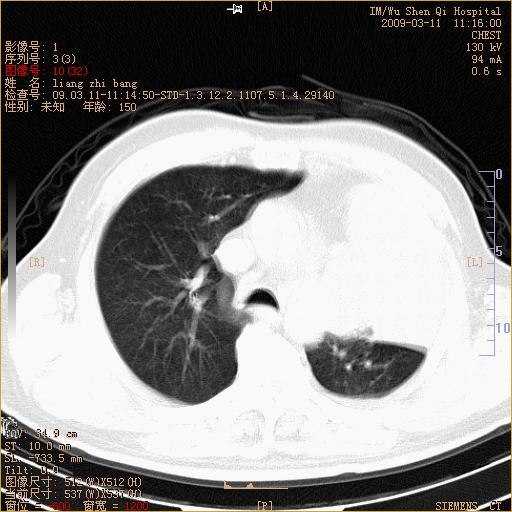

标题: CT18604:男,60岁,咳嗽一月余 [打印本页]

标题: CT18604:男,60岁,咳嗽一月余

1)考虑左肺上叶中央型肺癌并左肺上叶肺不张;建议必要时行纤支镜检查进一步明确诊断。2)左侧胸腔积液。

肺门肿块、支气管开口闭塞伴肺不张及胸水!典型的中心型肺癌变现!

1、左肺上叶中央型肺癌并上叶阻塞性肺不张。

2、左侧胸腔少量积液,右侧胸膜轻度增厚。

左肺们肿块并左肺上叶不张。考虑左肺中心性肺癌并左肺上叶不张及左侧胸腔积液